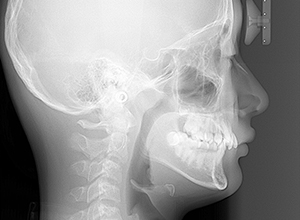

X-Ray

X-Ray所見

セファロ所見 下顎骨は比較的バランスが良いもののセラに対して下顎等は後方に位置しており中顔面部の奥行きもあることから顔面高さは低くなっていた。

パノラマ所見 上下顎第三大臼歯は埋伏歯しており、上顎右側犬歯は先天欠如をしていた。